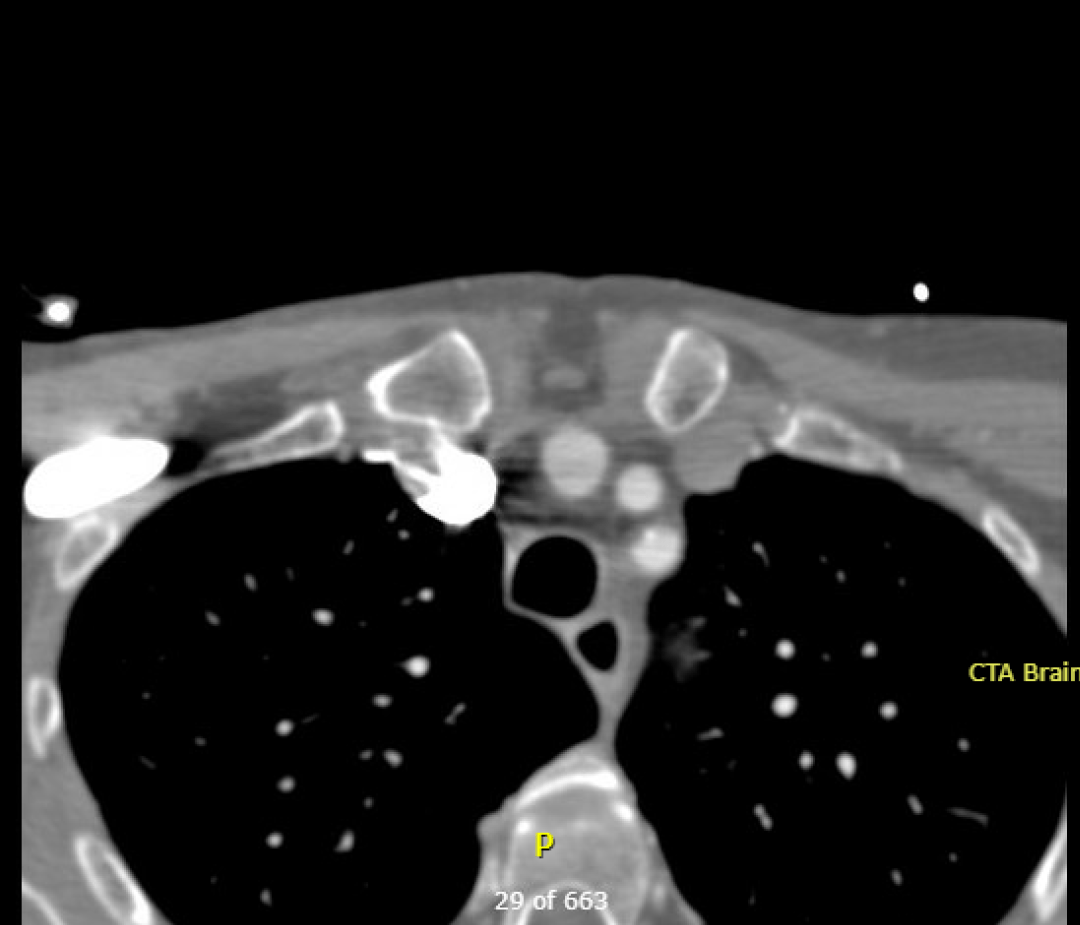

Name the three major branches off the aortic arch, as seen on this axial CTA: